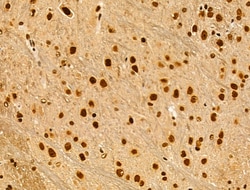

Invitrogen™ Phospho-AKT1 (Ser124) Polyclonal Antibody

Antibody detects endogenous levels of AKT1 only when phosphorylated at Ser124.

| Immunohistochemistry (Paraffin), Western Blot, Immunocytochemistry | |

| Human, Mouse, Rat | |